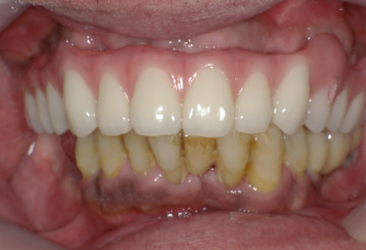

前歯に連結固定した差し歯が入っています。おそらく奥歯がなりなり、噛めなくなるので、前歯でしっかり噛めるように連結固定したのだと思いますが・・

治療前の写真です。前歯がぐらぐらになっています

奥歯がなくなり、前歯ばかりで噛んでいるとフレアーアウトといって前歯がどんどん前に傾いて出てきます。

術後の写真です。フレアーアウトした分、歯を引っ込めてかみ合わせも若干高くしています。

術前の口元と別人になっているのが分かると思います。

オールオンフォーの良いところはこのように好きなように歯を並べることができることです。